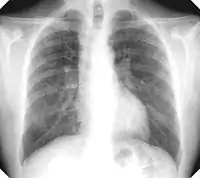

Complicated silicosis

Silicosis ILO Classification 2-2 R-R